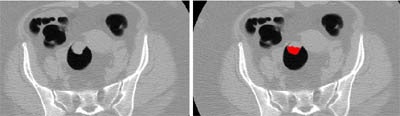

![]() |

| Polypoid mass in the rectosigmoid colon (left, center), red region (right, center) indicates the mass region extracted by the CAD scheme for the detection of masses. Images courtesy of Dr. Hiro Yoshida. |